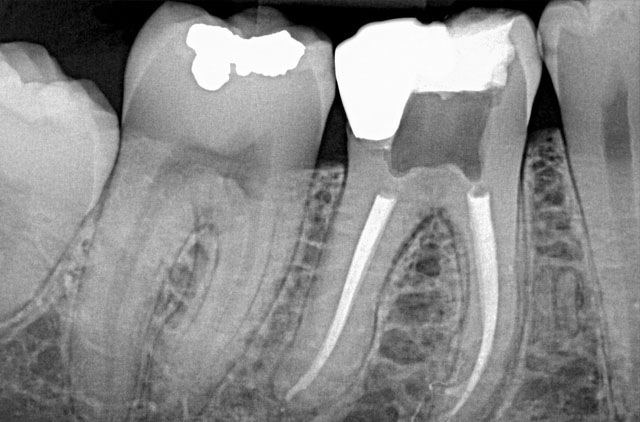

RADIOGRAFÍA PERIAPICALES

-Periapicales

-Oclusal

-Serial Periapical Infantilm (10 Rx)

-Serie Periapical Adulto (14 Rx)